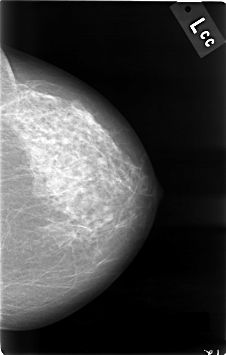

C_0001_1.LEFT_CC

LEFT_CC LINES 4608 PIXELS_PER_LINE 2928 BITS_PER_PIXEL 12 RESOLUTION 50 NON_OVERLAY